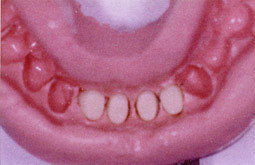

Une femme de 42 ans a été adressée du service de parodontologie. Lexamen endobuccal révèle la présence abondante de tartre au niveau des incisives inférieures 32-31-41-42 (Fig.1) . L'examen radiographique montre une alvéolyse terminale au niveau du secteur antérieur.